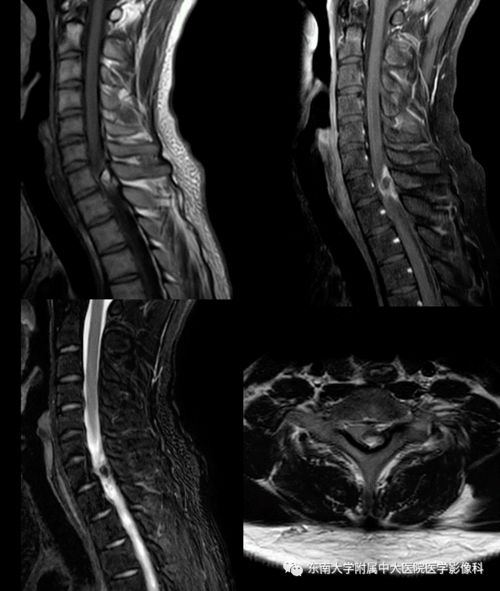

腰椎间盘突出是指腰椎间盘的纤维环破裂,导致髓核突出压迫神经根或脊髓。腰椎间盘突出常见于中老年人,尤其是长期从事重体力劳动或久坐不动的人群。腰椎间盘突出的症状包括腰痛、下肢放射痛、麻木、无力等。治疗腰椎间盘突出的方法包括药物治疗、物理治疗、牵引和手术治疗。